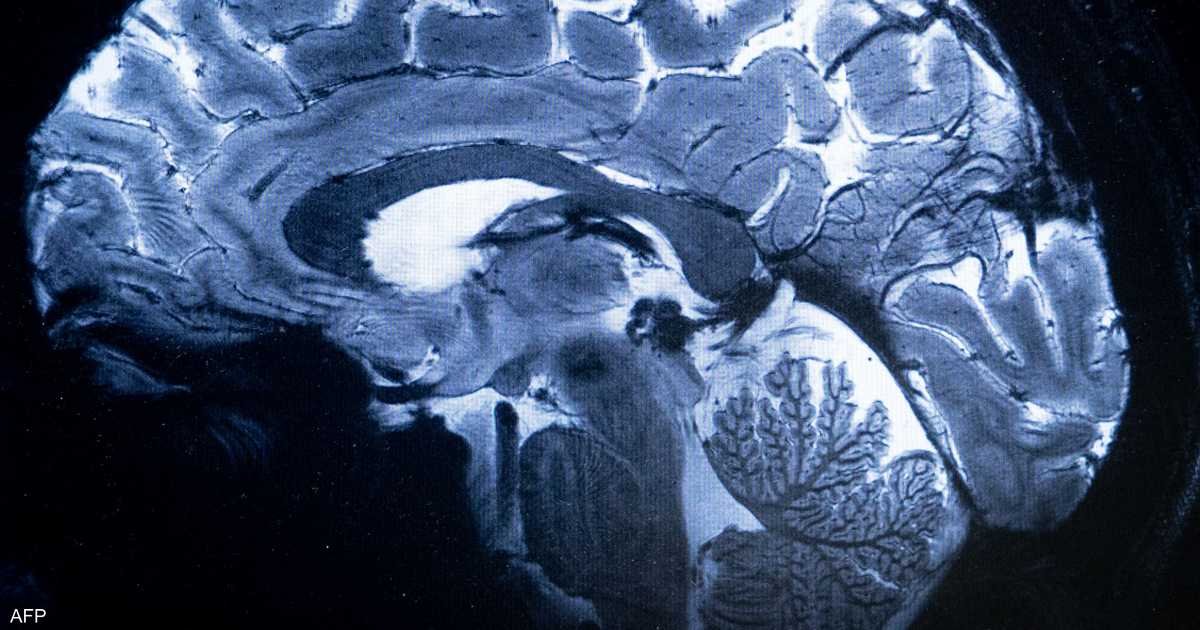

وفي عام 2012، توصل فريق بحثي بجامعة روشستر الأميركية برئاسة اخصائية طب الأعصاب مايكن نيدرغارد إلى وجود نظام دوري لم يكن معروفاً من قبل لطرد الفضلات السامة من المخ.

وتبين من خلال أبحاث على فئران التجارب تدفق السائل النخاعي داخل أنفاق حول الأوعية الدموية في المخ، حيث تمر هذه القنوات على نوعية من خلايا المخ تعرف باسم الخلايا النجمية وتختلط بما يعرف باسم “السوائل الخلالية”، حيث تقوم بجمع الفضلات وتحملها خارج المخ عبر المساحات حول الأوعية الدموية.

وقد أمضى الباحثون السنوات العشر الماضية في دراسة ما إذا كانت عملية اغتسال المخ تحدث لدى الإنسان على غرار ما يحدث في حالة الفئران، وقد توصلت الأبحاث إلى إثبات صحة هذه النظرية، بل وأن الموجات الكهربائية التي تتحرك داخل المخ أثناء النوم، تقوم بدفع السائل النخاعي داخل المخ وخارجه.

ومن جانبه، يؤكد جيفري إيليف استاذ طب النفس والأعصاب بجامعة واشنطن أهمية ما يعرف باسم النظام “الجليمفاوي” الذي يقصد به آلية تنظيف المخ وإزالة الفضلات التي تتم أثناء نوم الإنسان.

ويقول في تصريحات لموقع “ساينتيفك أميركان” أن تعطل هذه المنظومة يؤدي على الأرجح إلى الإصابة باضطرابات عصبية ونفسية من بينها مرض الزهايمر، ويرى أن تعطل النظام الجليمفاوي قد يفسر سبب اختزان المخ لبروتينات الأميلويد وتاو في مرحلة الشيخوخة.